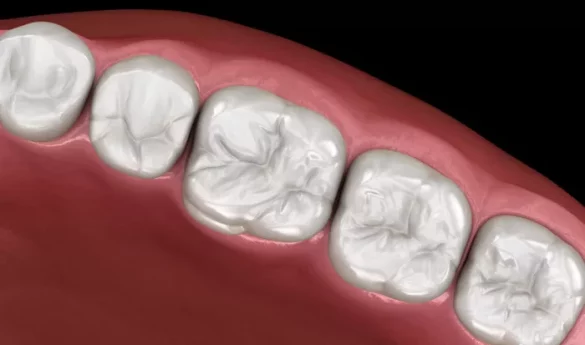

The dentist applies the resin in layers, curing each one with a special blue light. The material is shaped to match the natural contours of the tooth.

Once hardened, the filling is polished to create a smooth, tooth-like surface that resists staining and blends with adjacent teeth.

One of the most significant benefits of resin fillings is their ability to match the color of natural teeth, making them virtually invisible when you smile or talk.